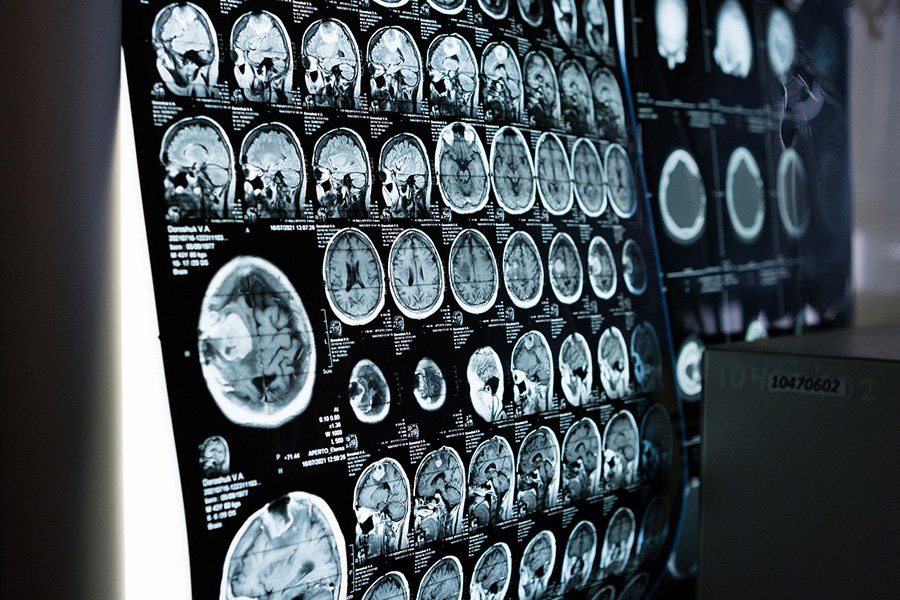

ИИ может определить пол человека по сканированию мозга с точностью до 90 процентов

Вопрос о том, можем ли мы измерить различия между мозгом мужчин и женщин, уже давно является спорным, а предыдущие исследования дали противоречивые результаты. Теперь ИИ может различать снимки мужского и женского мозга с точностью около 90 процентов.

Чтобы решить этот вопрос по-другому, команда Менона использовала относительно новый метод, называемый фМРТ динамической функциональной связи. Это включает в себя запись активности мозга людей, пока они лежат, в функциональном МРТ-сканере и отслеживание изменений в том, как активность различных областей изменяется синхронно друг с другом.

Исследователи разработали ИИ для анализа таких данных сканирования мозга, которые они обучили на результатах примерно 1000 молодых людей из существующей в США базы данных под названием Human Connectome Project, сообщая ИИ, какие люди были мужчинами, а какие женщинами. В этом анализе мозг был разделен на 246 различных областей.

После этого процесса обучения ИИ с точностью около 90 процентов различал второй набор данных сканирования мозга тех же 1000 мужчин и женщин.

Что еще более важно, ИИ одинаково эффективно различал снимки мозга мужчин и женщин из двух разных наборов данных сканирования мозга, которых он раньше не видел. Оба они состояли из примерно 200 человек примерно одного возраста от 20 до 35 лет из США и Германии.